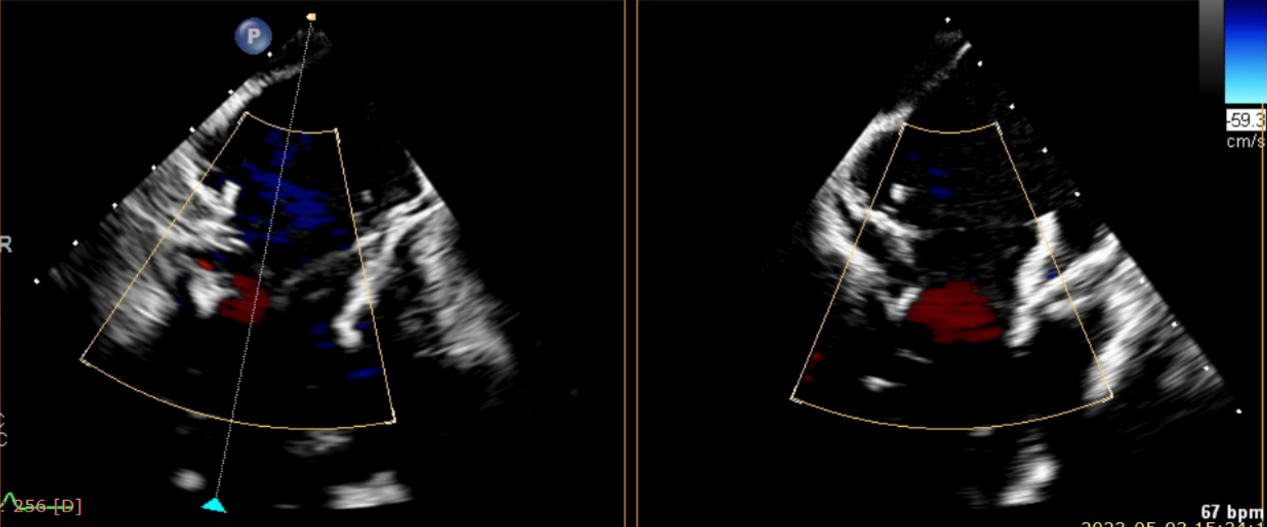

術前超聲提示大量三尖瓣反流

術中輸送器在超聲引導下調整位置

術后超聲提示僅殘余輕微瓣周漏